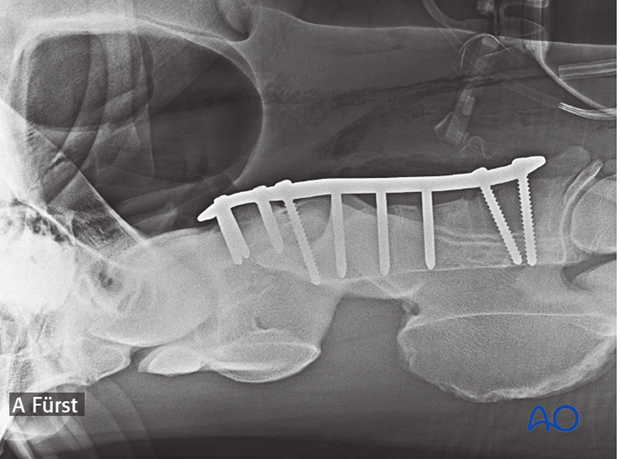

During the second surgery longer screws were used, which resulted in a much more stable fixation.

The remaining holes are filled with locking-head screws.

The use of a locking compression plate (LCP) is preferred for fracture fixation of the vertebrae. According to the size of the patient, a small or broad 3.5/4.0 or 4.5/5.0mm LCP is used.